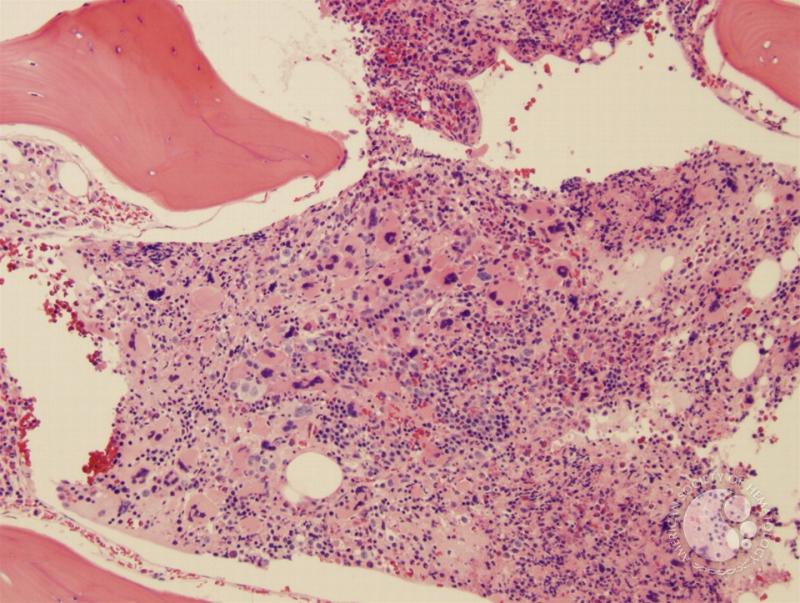

Myelofibrosis is a chronic disorder characterized by the abnormal proliferation of bone marrow cells leading to severe fibrosis or scarring of the bone marrow, which disrupts the body’s ability to produce blood cells properly. This condition falls under the umbrella of myeloproliferative neoplasms and typically presents with symptoms such as fatigue, anemia, enlarged spleen (splenomegaly), and bone pain. Treatment for myelofibrosis has evolved significantly over recent years, incorporating both conventional therapies and novel agents targeting the molecular abnormalities driving the disease.

Allogeneic hematopoietic stem cell transplantation (HSCT) remains the only potentially curative treatment for myelofibrosis. This intensive procedure involves replacing the patient’s diseased bone marrow with healthy donor marrow, which helps restore normal hematopoiesis and may reverse fibrosis. However, due to the high risk of complications and treatment-related mortality, HSCT is typically reserved for younger and high-risk patients with acceptable performance status.